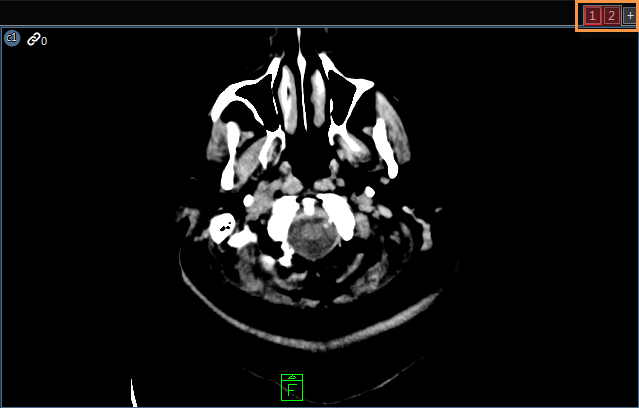

A virtual monitor is one that is defined in a layout but does not physically exist on the workstation. Virtual monitors (highlighted below) are located on the top right corner of the image viewing area. An example of when virtual monitors appear is when a hanging protocol is defined to use two monitors when it is applied on a workstation with only one monitor. The layout applied to the second monitor is created and initialized however, because only one monitor exists, it cannot be rendered. To create a virtual monitor, select the + located in the top right corner (highlighted).